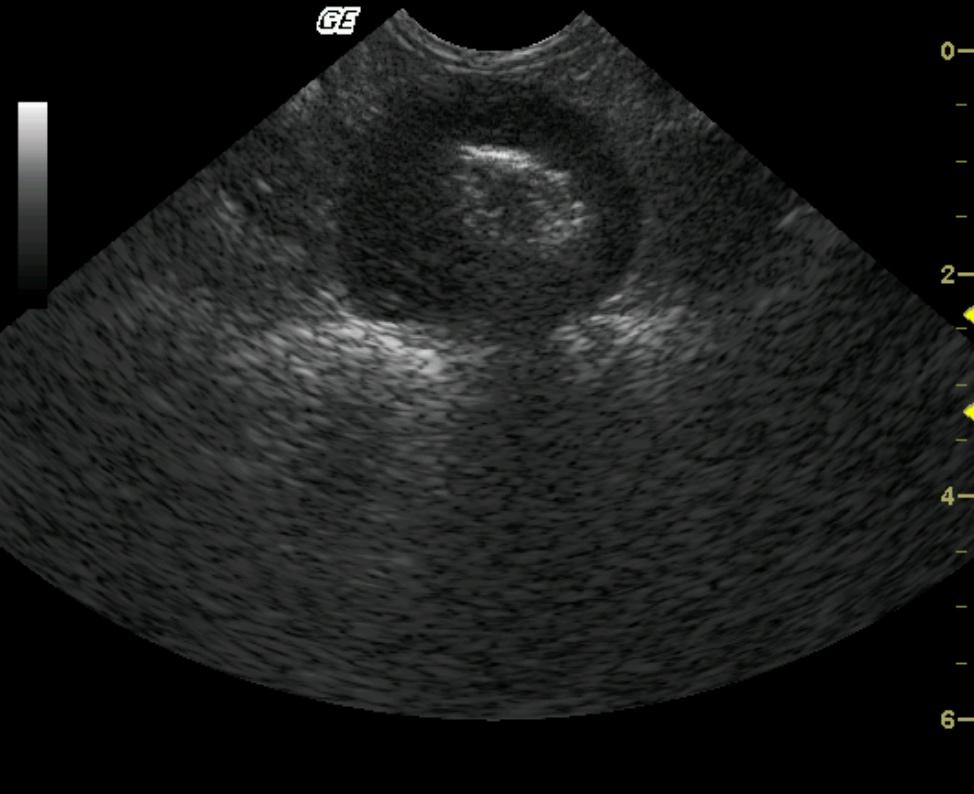

Image Interpretation

A round, intestinal wall mass was noted in the small intestine with loss of mural detail. The hyperechoic central lumen identifies the mass as intestinal in origin. The biopsy track crosses into the lumen which is not ideal as it may allow for luminal contamination of the abdominal cavity as well as the pathology sample potentially causing a septic enteritis diagnosis as opposed to a neoplastic one.

Sampling

U/S-guided Tru-cutВ® biopsy of intestinal thickening revealed alimentary lymphoma.